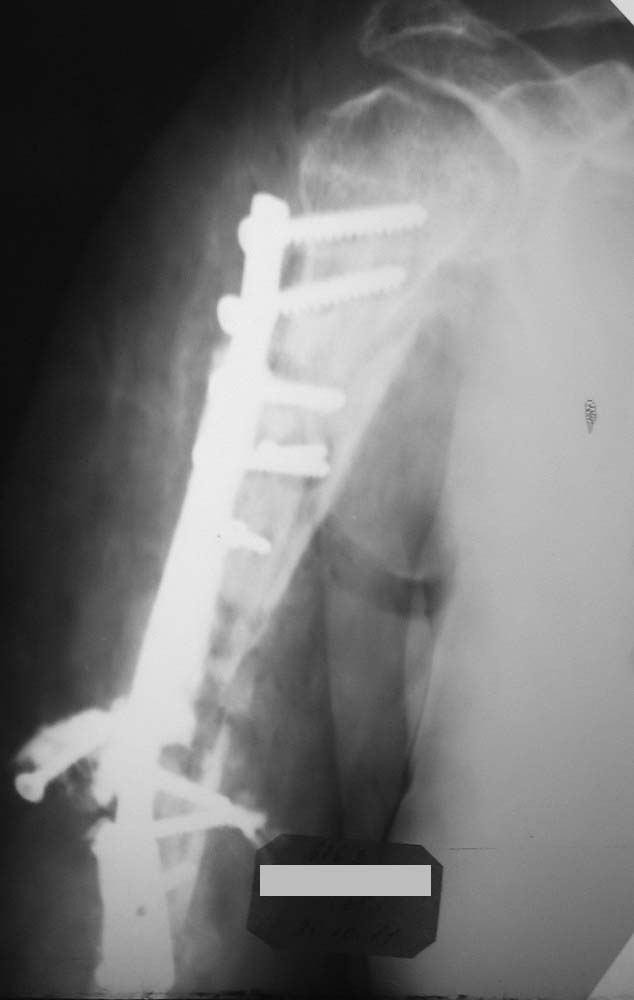

Больная 65 лет. Травма в июле 2011 года – закрытый оскольчатый перелом в/3-с/3 правого плеча со смещением.

Оперативное лечение через 2 недели после травмы (позднее обращение больной) – открытая репозиция, МОС пластиной.

В октябре 2011 года – повторная травма правого плеча, после которой появился свищевой ход в области с/3 плеча. После выполнения фистулографии произведено повторное оперативное лечение – удаление МОС, фистулсеквестрнекрэктомия, КДО стержневым аппаратом, проточно-промывное дренирование. П\о рана зажила первичным натяжением.

Хотелось бы обсудить тактику дальнейшего лечения.

Варианты: 1) МОС блокируемым штифтом+костная пластика.

2)Сращение правого плеча в аппарате с укорочением (смущает длина дефекта диафиза)